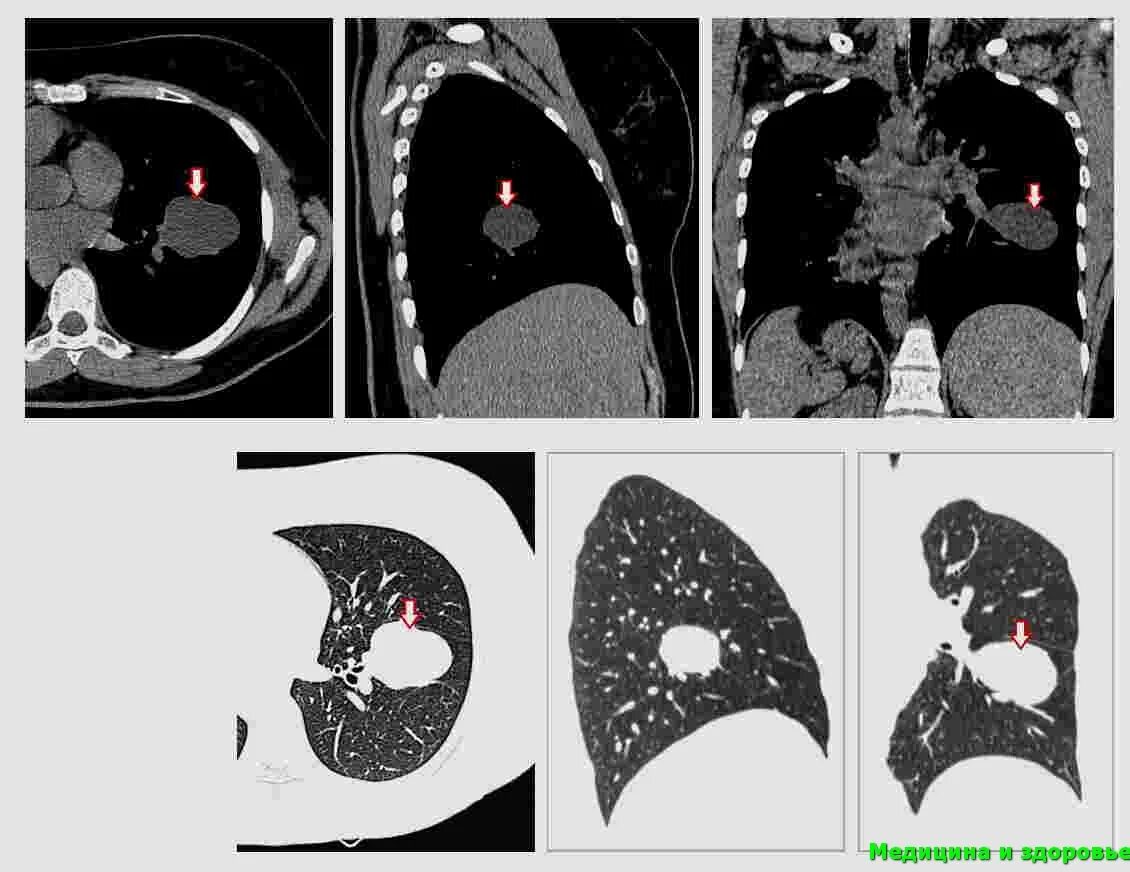

Метастазы плевры